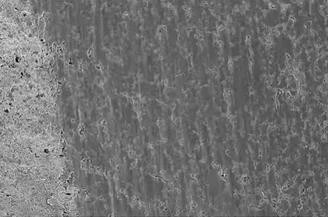

合成材料滲透陶瓷如復(fù)合材料一樣,由有機和無機部分組成(圖8至13)。與復(fù)合材料不同的是,先產(chǎn)生一個開放多孔的框架,然后由聚合物滲透15,16。合成材料滲透陶瓷的優(yōu)點是,其彈性模量類似于天然的牙齒結(jié)構(gòu)。這種雜化材料的機械和化學(xué)性能位于聚合物和玻璃陶瓷的性能之間。針對這種結(jié)構(gòu)的理解也可以比喻為:主框架是由陶瓷(目前玻璃陶瓷)做成的海綿,海綿的孔隙用合成材料填充,因此產(chǎn)生兩個結(jié)合系統(tǒng),即陶瓷和合成材料基系統(tǒng)。在掃描電子顯微鏡圖像上觀察,在咀嚼模擬后可以清楚地看到陶瓷網(wǎng)結(jié)構(gòu)(圖左半側(cè))(圖13)。

圖13:在模擬咀嚼后,一個由混合陶瓷制作的修復(fù)體冠的SEM圖像(圖片來源:MaxHummel 博士)。